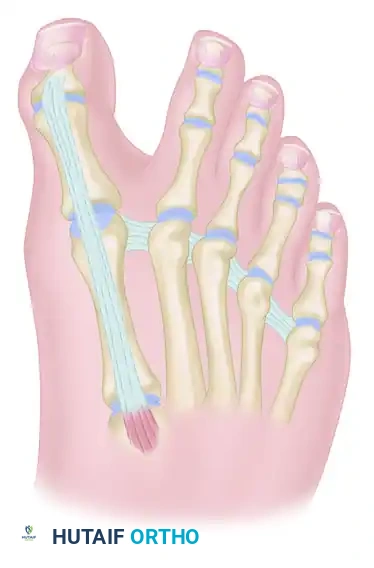

Step 5: EHL Tendon Routing and Transfer

With the IP joint securely fused, attention is turned to the dynamic correction of the MTP joint. The goal is to route the EHL tendon to act as a lateral collateral ligament substitute and a plantarflexor.

- Identify the deep transverse metatarsal ligament in the first web space.

- Pass the mobilized EHL tendon plantar to the deep transverse metatarsal ligament. This critical step changes the vector of the EHL pull from dorsal-medial to plantar-lateral.

- Route the tendon dorsally to the base of the proximal phalanx.

- Prepare a drill hole through the base of the proximal phalanx from lateral to medial. Pass the EHL tendon through this osseous tunnel.

- Apply tension to the EHL tendon while holding the MTP joint in approximately 10 to 15 degrees of extension and neutral coronal alignment (correcting the varus).

- Suture the tendon back onto itself using non-absorbable braided suture (e.g., #2-0 FiberWire or Ethibond) to secure the transfer under appropriate physiological tension.

Clinical Pearl: The tensioning of the EHL transfer is the most technically demanding aspect of the procedure. Over-tensioning will result in a rigid, plantarflexed MTP joint that causes significant pain during the toe-off phase of gait. Under-tensioning will fail to correct the varus deformity. The toe should rest naturally in neutral alignment without manual support once the tendon is secured.